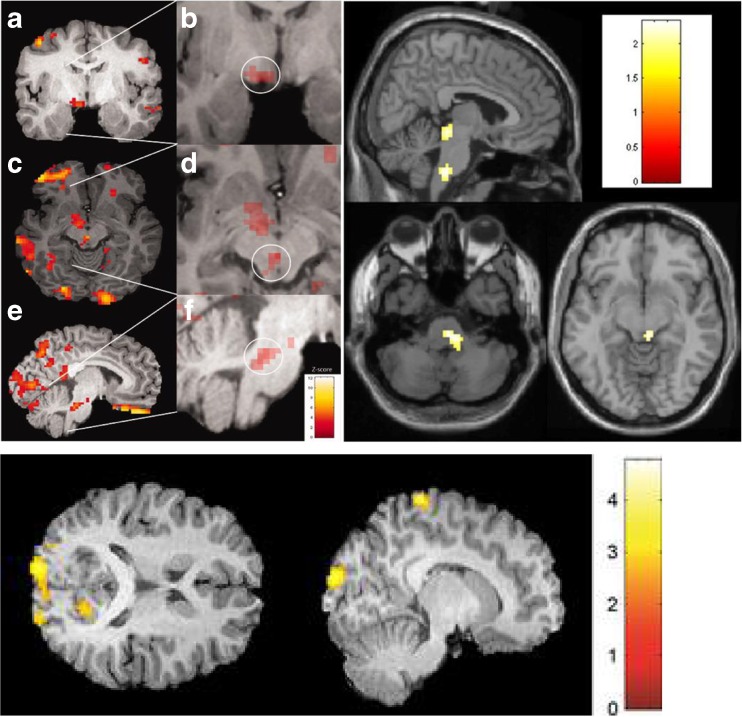

Yawning is a partially dopamine-mediated symptom [31–33] and has been consistently commonly reported in adult studies of premonitory symptoms in migraine, suggesting that dopamine may be a neurotransmitter involved early in a migraine attack. Indeed small studies in the past have shown that domperidone, a selective D2 dopamine antagonist, taken during the premonitory phase may be effective at preventing headache onset [34, 35]. Of the 100 children in our study 30% reported yawning as a premonitory symptom [26••]. It was also reported in 11% of patients in the Cuvellier study [25]. The origin of this yawning in migraine may be hypothalamic, given Maniyar et al.’s imaging study showing early hypothalamic activation in a functional imaging study during the premonitory stage of migraine [22•]. See Fig. 2.

Fig. 2.

Brain areas activated during the premonitory stage of migraine attacks in the adult imaging studies. Upper left – Brainstem areas, including dorsolateral pons, activated, as well as periaqueductal grey and various cortical areas [22•]. Upper right – Nausea imaged in the premonitory phase, showing likely nucleus of tractus solitarus activation [23•]. Bottom left – Photophobia imaged in the premonitory phase, showing occipital cortex activation [24]. All images published with permission from the authors. Image taken with journal permissions from [23•]

These symptoms may be limbic system mediated; in particular the anterior cingulate cortex (an important part of the frontal lobe which is vital to emotional processing in pain) has also been shown to be activated during the premonitory phase [22•]. Additionally, fatigue and sleep and wakefulness disturbance may also arise from hypothalamic-brainstem connections [37]. See Fig. 2.

The perception therefore of neck stiffness in the premonitory phase, could be through early activation of brainstem and diencephalic structures such as the hypothalamus, with loss of inhibitory input to trigeminal afferent signalling and upper cervical connections [39]. Additionally the other brainstem areas such as PAG and LC may also be active early in the premonitory phase [22•] and have similar roles in migraine in facilitating such symptoms. See Fig. 2.

Photophobia in the premonitory phase has been shown to be centrally mediated, through activation of the occipital cortex [24]. How this occipital cortex activation comes about is likely to be through ascending activation from the brainstem through the thalamus [40, 41]. Functional imaging studies have helped us develop some understanding of how early brainstem activation during the premonitory phase may cause upstream cortical activation through thalamic processing before pain has started. See Fig. 2.

Similarly a functional imaging study has helped us locate the origin of nausea in the premonitory phase [23•]. Although less commonly reported by children compared to adults (25% of adults reported nausea in the Giffin et al. study) [14], it has been another consistent symptom reported in the adult literature. The nucleus of the tractus solitarius has been implicated in experimental and imaging studies, again located within the brainstem [23•, 42]. See Fig. 2.

It is also clear that decades of work have culminated in the current theory that the brainstem is the pivotal area in migraine generation [43] and pilot imaging studies during the premonitory phase in adults have shown it to be involved early and have also hypothesised the involvement of particular, mainly subcortical brain areas, during the premonitory phase which may lead to a loss of inhibition over other trigeminal nociceptive areas and the perception of pain [22•, 23•, 24]. How this loss of inhibition comes about and whether there is a threshold effect as to whether migraine headache ensues after premonitory symptoms (we have observed premonitory-like symptoms without subsequent headache development in an experimental human migraine model) [30••] is an area which requires further work.